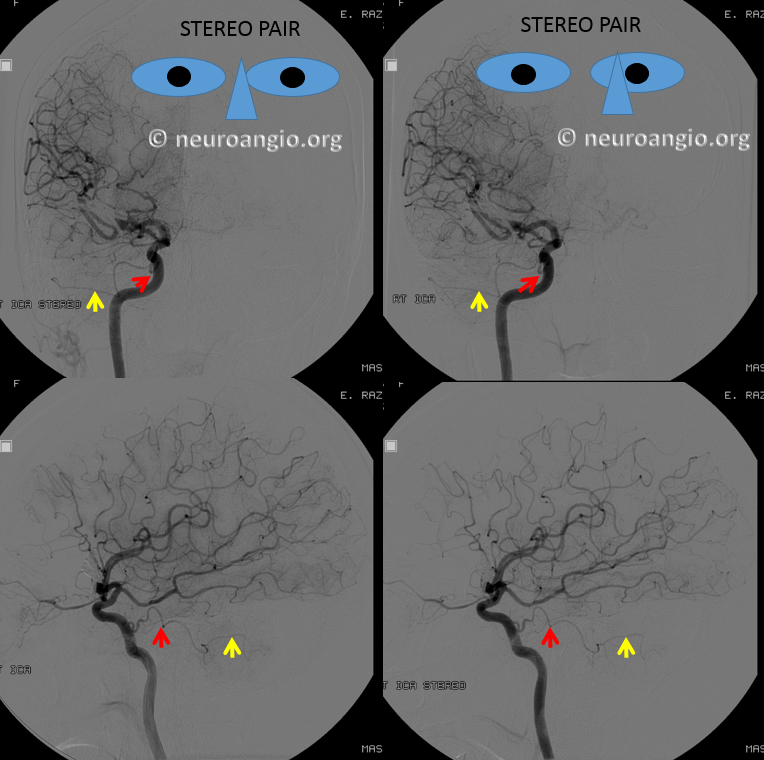

Trigeminal Artery and PCOM fenestration — not only does this person have a PCOM, but a fenestrated one — a finding that is exceedingly rare — I’ve only seen one. There is one report of it in the literature, however this report does not seem to have images. So, this one is the only fenestrated PCOM image in the world I know of — except for all the ones being hidden somewhere for no useful purpose. Therefore, if you have any, please SHARE — like they told you in childhood. Credits guaranteed. Stereoscopic image below courtesy of Dr. Nelson and Dr. Becske

Anaglyph